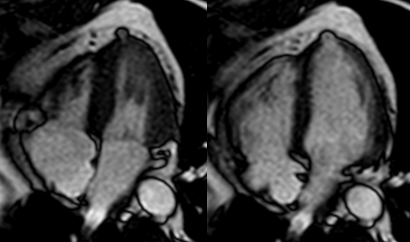

Figure 1 Doppler echocardiogram, apical 2-chamber view: At the level of the apex there is evidence of evagination in the dyskinetic myocardial wall and apparent thinning, with evidence of color filling inside, neck measured 0.95 cm.

Figure 2 2-chamber echocardiography sequence: At the apex level, the presence of a microaneurysm (saccular evagination, "gloved finger", of the myocardial wall, which is severely thinned: 1.5mm and dyskinetic) is visualized.